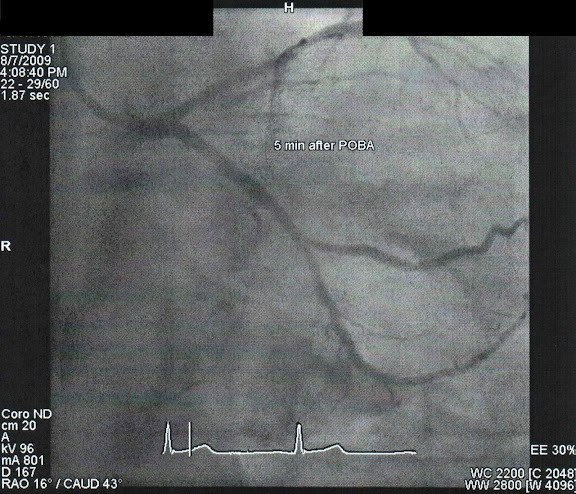

撐開之後血流就正常多了。

等個5min後再觀察看看堵塞處有沒有縮回來,如果縮回來的話就一定要放支架了。

等待5min過後,看起來有撐開沒再縮回去。